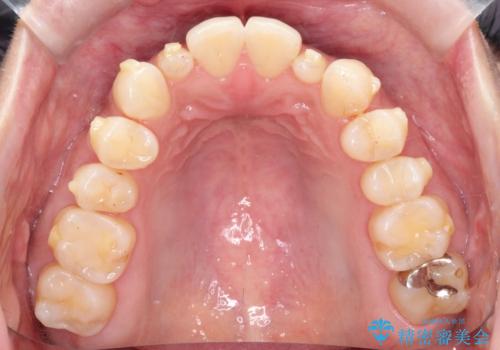

【インビザライン】矮小歯を有する方の矯正治療

- 前歯の凸凹を主訴に来院されました。

元々、歯が小さかったため矯正終了後にセラミックにて修復治療を行う治療計画をたてインビザラインにて治療を行いました。

今回はスペースを作るために歯列の拡大をメインでおこなっています。